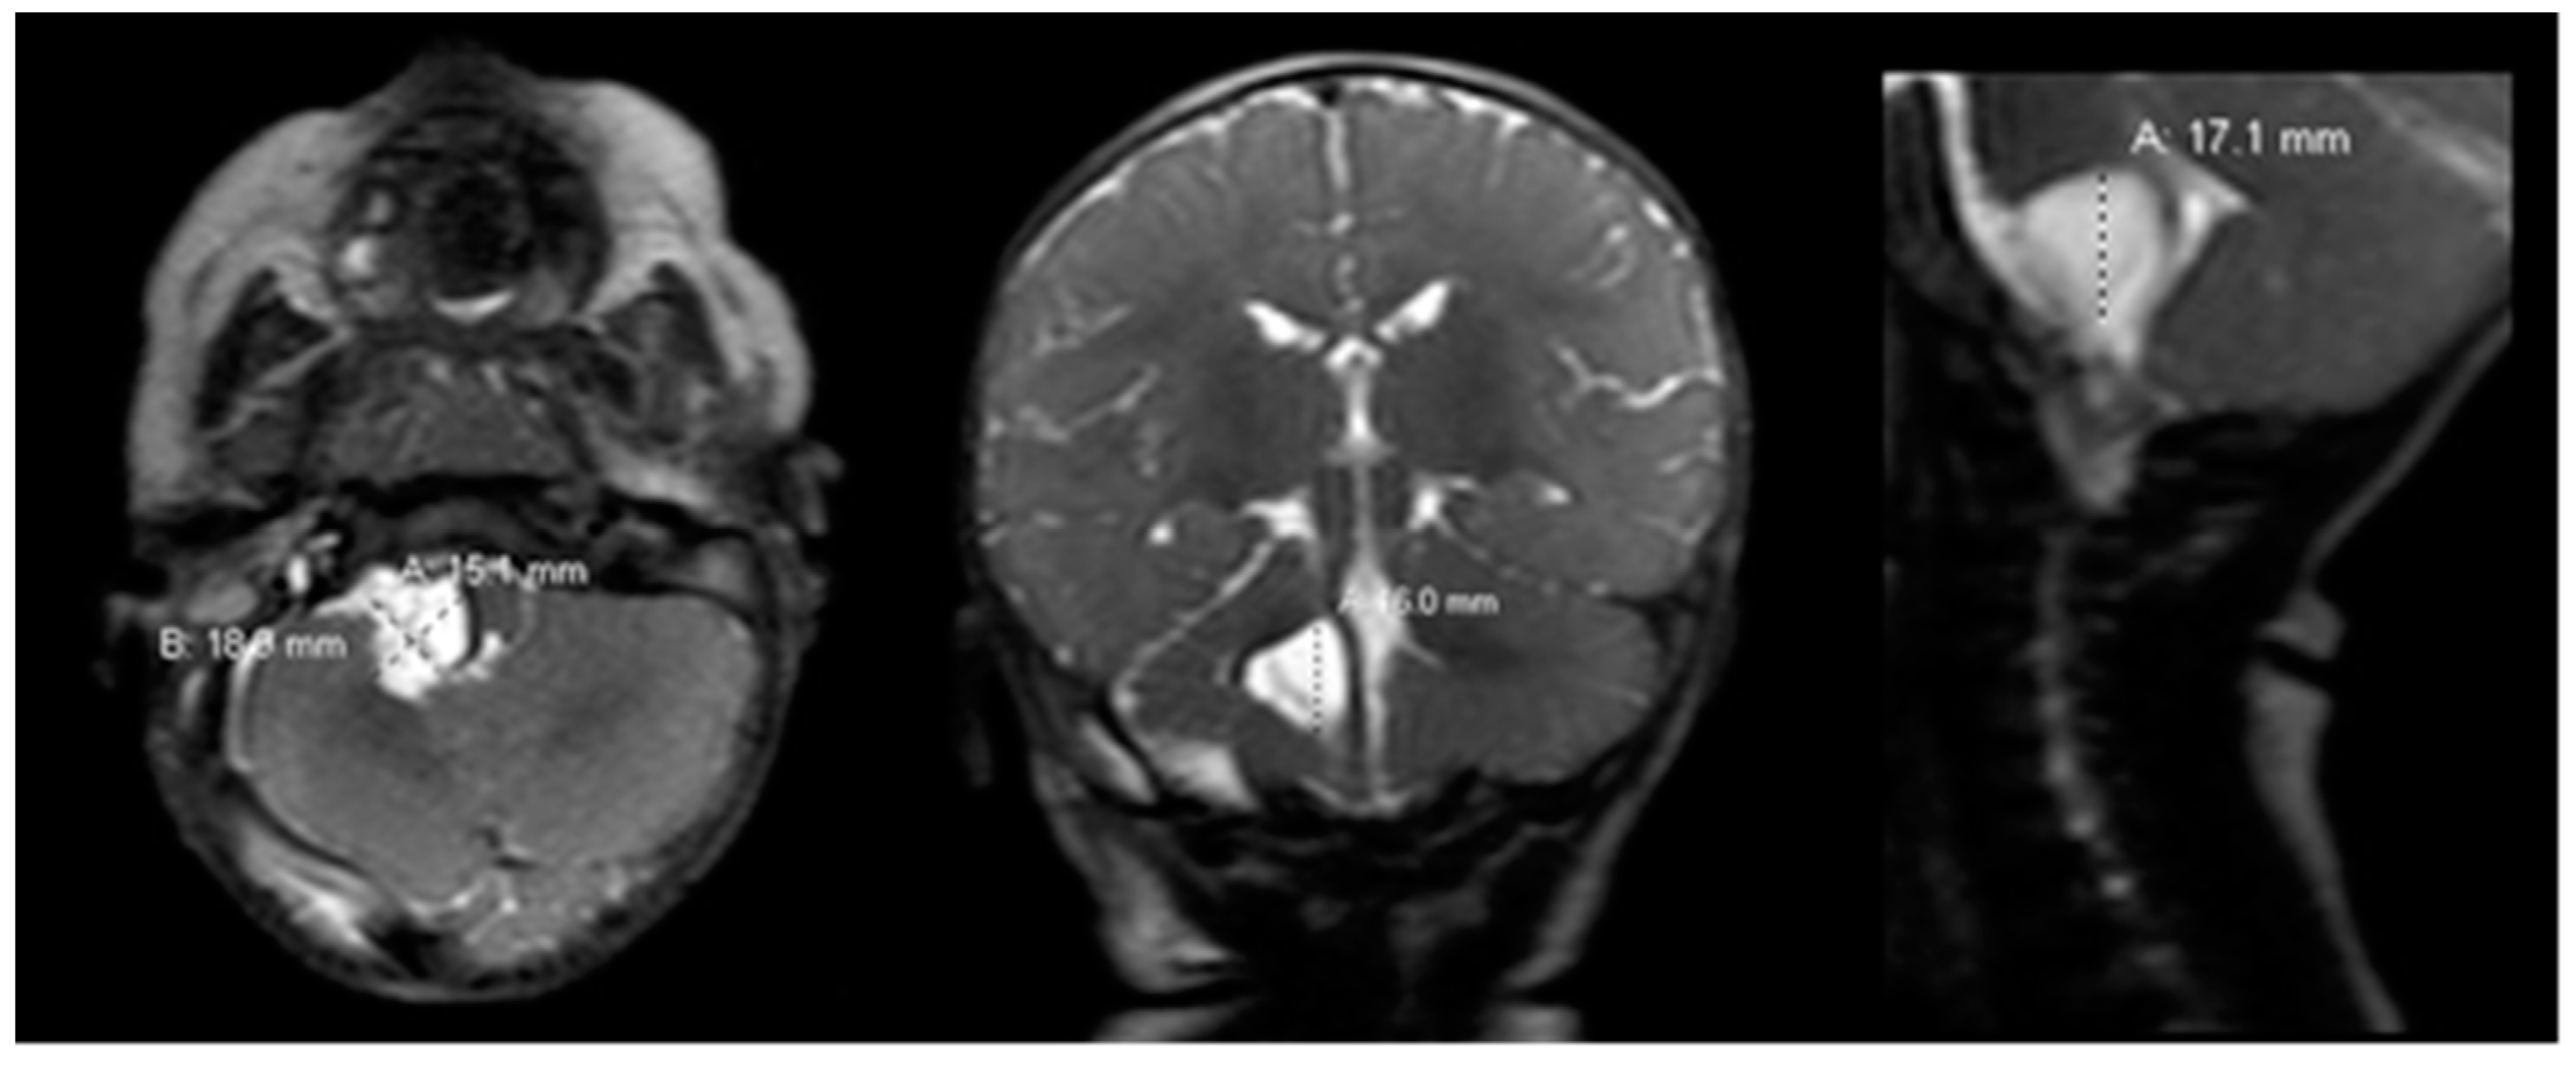

Preoperative magnetic resonance imaging (MRI) of the brain and cervical spine was obtained as the patient’s respiratory difficulties and failure to thrive suggested a lesion localizing to the brainstem. MRI showed a large cystic lesion at the right CPA measuring 2.7 × 2.5 × 3.0 cm (anteroposterior (AP) × transverse (TV) × cephalocaudal (CC), respectively), hypointense on T1 and hyperintense on T2, without gadolinium enhancement, diffusion restriction or susceptibility artifact, most consistent with an arachnoid cyst (Figure 1). The lesion was causing overt flattening of the pons and mass effect along the length of the right superoanterior and lateral medulla, mild mass effect on the right cerebellum, and displacement and mild effacement of the fourth ventricle. There was no abnormal vascularity, syrinx or chiari malformation or extension down to the cervical spine. Ventricles were otherwise normal in morphology and size.

Figure 1.

Preoperative brain MRI scan. The preoperative brain MRI scan (left = axial; middle = coronal; right = sagittal) T2 sequences showed a large 2.5 × 2.7 × 3.0 cm homogeneous, hyperintense right cerebellopontine angle cystic lesion causing mass effect on the right pons and medulla. T1 sequences (not shown) were hypointense for the cyst, without contrast enhancement on gadolinium scans. MRI = magnetic resonance imaging.